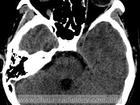

空泡蝶鞍综合症

图片尺寸677x476